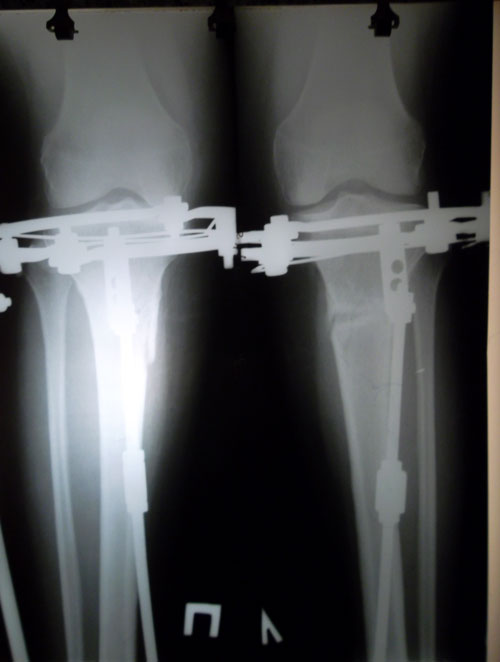

Исходник.

Дата операции 01.07.2014г.

Внутренний контур голеней слабо выражен или практически отсутствует.